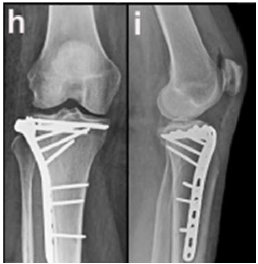

Enunciado 4335220-1

A respeito da técnica empregada na osteossíntese do platô tibial nesse caso, é correto afirmar que a placa lateral